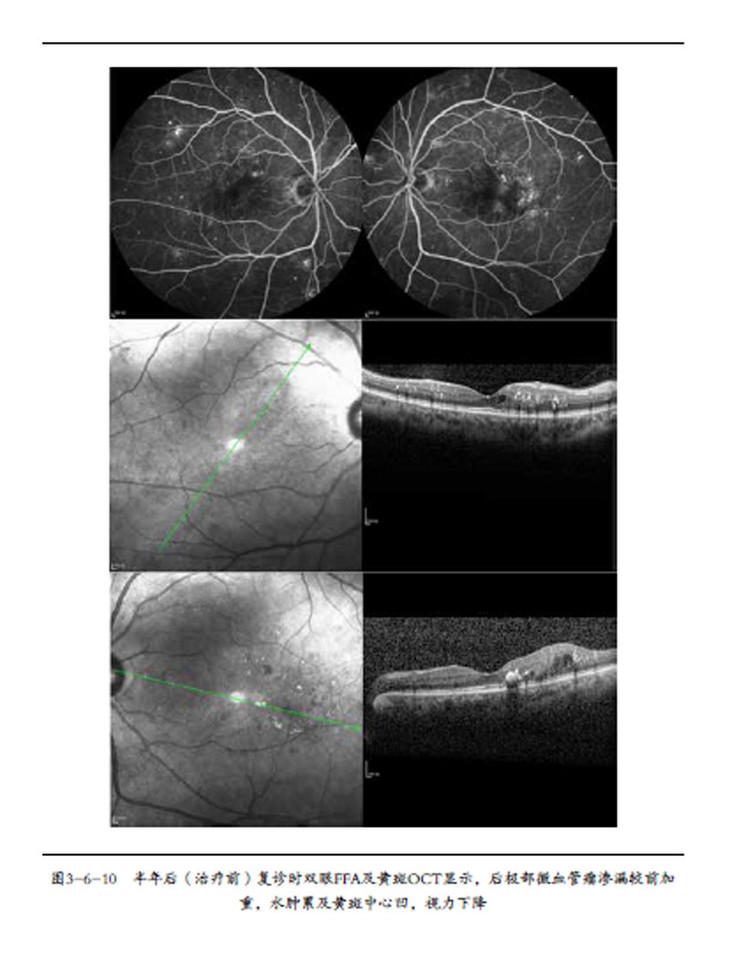

第二节 糖尿病性视网膜病变的荧光素眼底血管造影/ 050

第三节 光相干断层扫描成像技术在糖尿病性视网膜病变的应用/ 059

第七节 糖尿病性黄斑水肿的临床防治/ 119